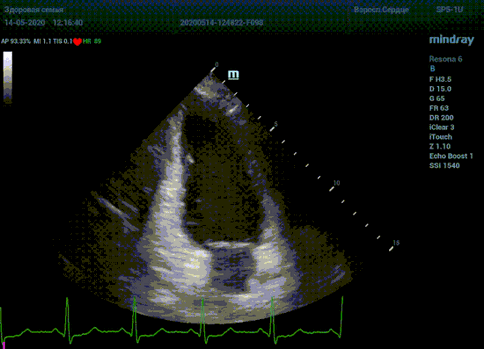

С появлением В режима реализовалась возможность визуализации всех сегментов миокарда из парастернальных и апикальных сечений. Метод Teicholtz в широкой практике сменился методом дисков. Метод дисков, или метод Simpson, позволяет разбить левый желудочек на 20 дисков, с расчетом объема каждого из них. Используя 2 перпендикулярных сечения, апикальные двух и четырех камерное, мы приближаемся к значению реального объема левого желудочка. Исследователь обводит интерфейс эндокард – кровь в фазу диастолы и фазу систолы. Линия простирается от кольца митрального клапана и до кольца митрального клапана, четко разграничивая объем желудочка от предсердия. Для достоверного изменения необходимо использовать ЭКГ канал.

Обводить вручную эти линии занимало много времени, однако результат того стоил. Следующим шагом стало появление Spline технологии, позволяющее расставлять точки и автоматически их соединять. Такой способ планиметрии контура эндокарда значительно сократил время измерения.

Что могут предложить современные приборы? Приборы нашего времени являются мощными вычислительными машинами, способными обрабатывать полученную информацию даже без помощи человека. Система автоматического вычисления фракции выброса – AUTO EF на приборах серии Resona компании Mindray сделает все за вас. За пару секунд прибор сам отыщет нужную фазу сердечного цикла и произведёт измерение и расчеты, а также покажет график изменения объема в сердечном цикле. От Вас требуется только получить качественное 4С и 2С сечение. Впрочем, прибор всегда оставляет возможность коррекции, если доктор имеет свое мнение на расположение точек планиметрии или момента измерения по ЭКГ каналу.